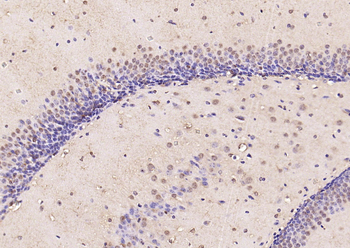

100 μl, 200 μl, 50 μlPhospho-SMAD5 (Ser463 + Ser465) Recombinant Rabbit Monoclonal Antibody [orb559123]

ICC, IF, IHC-Fr, IHC-P, WB

Mouse, Rat

Human, Mouse, Rat

Rabbit

Recombinant

Unconjugated

50 μl, 100 μlPhospho-Smad3 (Thr179) Rabbit Polyclonal Antibody [orb313112]